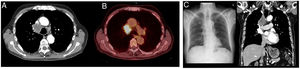

The patient's admission was prompted by symptoms including respiratory failure, asthenia, and atypical chest pain persisting for a week. A chest X-ray revealed mediastinal widening. In response to these findings, a computed tomography (CT) scan was performed, unveiling the presence of a solid mass in the mediastinal region and the right superior hilar area. This mass exhibited close proximity to the right tracheal margin, the right brachiocephalic trunk, the right main pulmonary artery, as well as the ipsilateral superior lobar pulmonary arteries and veins, suggesting possible infiltration (Fig. 1). Consequently, an endobronchial ultrasound-guided transbronchial needle aspiration (EBUS-TBNA) was conducted, enabling the diagnosis of the mass as lung adenocarcinoma and the identification of partial thrombosis within the superior vena cava, as illustrated in Video A.